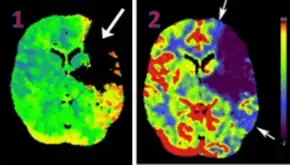

![]() CT perfusion with flow and volume maps in cerebral infarction | |

Perfusion CT or CT Perfusion is a type of Perfusion Scanning using Computed Tomography. It is helpful in evaluation of the vascularity of a tissue in the body. In this the temporal changes in the tissue density are measured which gives the information about the vascularity of the tissue. In CT perfusion injection of contrast media is given and then the scan is taken. The acquired data are then post-processed to obtain perfusion maps with different parameters, such as BV (blood volume), BF (blood flow), MTT (mean transit time) and TTP (time to peak).[1][2]

CT Perfusion plays an important role in the assessment of Acute Ischemia Stroke. It is used to create maps of blood flow, blood volume and mean transit time to assess the tissue and to differentiate between core and penumbra in stroke.[3]